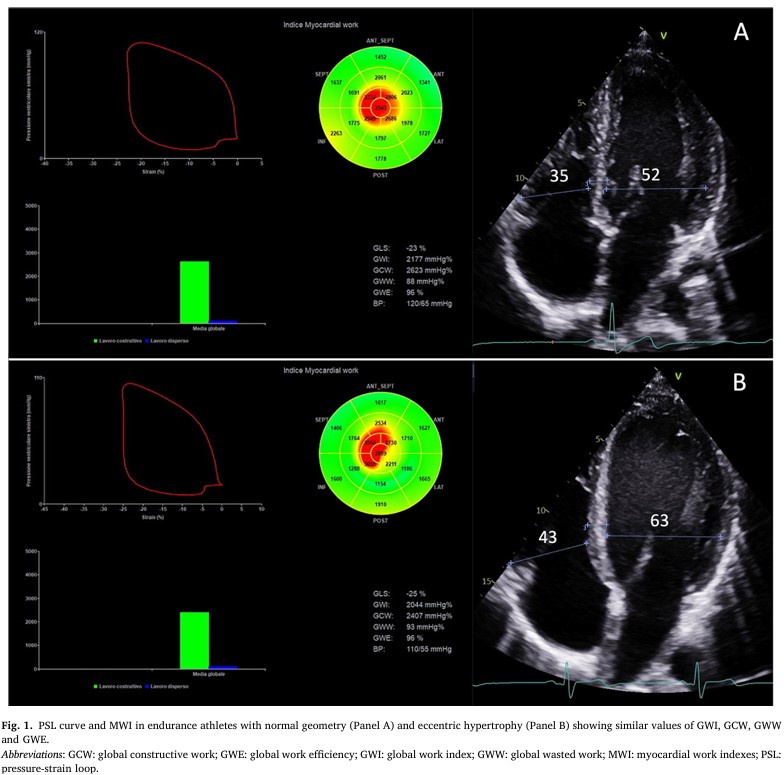

Não foram observadas diferenças em relação à fração de ejeção (FE), parâmetros de função diastólica e no strain global longitudinal (SGL).

Em relação aos parâmetros do trabalho miocárdico, o índice de trabalho miocárdico (GWI) foi similar (p = 0.668), bem como os valores de trabalhos construtivo (p = 0.862) e desconstrutivo (p = 0.439), além da eficiência global – GWE ( p = 0.832).

Os resultados mostram, portanto, que atletas com remodelamento cardíaco induzido pela atividade física de alta intensidade apresentam parâmetros normais de trabalho miocárdico, sem haver diferença significativa em comparação com aqueles atletas sem um remodelamento pronunciado.

Esses achados atestam a natureza fisiológica do remodelamento induzido pela atividade física em atletas de elite.

Assim sendo, além de confirmar a natureza fisiológica das alterações estruturais induzidas pela atividade física em atletas de endurance, o trabalho miocárdico pode auxiliar não só na diferenciação entre adaptação e doença (valores normais sugerem fortemente um fenômeno benigno enquanto que parâmetros alterados podem sugerir uma condição patológica), mas também fornecer informações sobre treinabilidade.